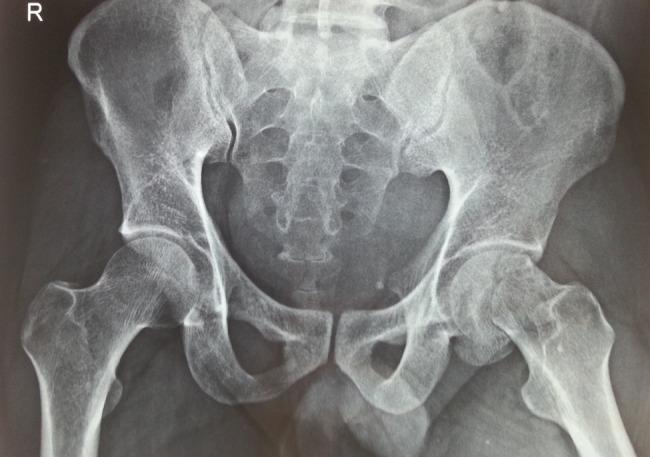

一种罕见的组合:同侧股骨颈头同时骨折且无髋关节脱位。

A rare medley: concurrent ipsilateral femur head and neck fracture without hip dislocation.

Simultaneous post-traumatic ipsilateral fracture of femur head and subcapital femur neck without hip dislocation is a rare presentation and easily missed on X-ray imaging. A 48 years old male, with a history of high-energy road traffic accident, presented to us with severe pain in the left hip region and inability to ambulate. Preliminary X-ray showed impacted subcapital fracture with varus angulation between femur head and neck. Further computed tomography (CT) scan imaging showed ipsilateral fracture of femur head and subcapital femur neck without hip dislocation. Primary total hip arthroplasty was performed. Presently patient is 5 years post-surgery and can ambulate without support. In conclusion, this fracture pattern, though rare, should be suspected in high-energy road traffic accident patients with shear forces acting at femur neck. It can best be diagnosed using 3D CT scan imaging. Primary total hip arthroplasty is an appropriate treatment in such patients.

摘要

创伤后同时发生的同侧股骨头和股骨颈基底骨折且无髋关节脱位是一种罕见的表现,在X线成像上很容易被漏诊。一名48岁男性,有高能道路交通事故史,因左髋部剧痛和无法行走前来就诊。初步X线显示股骨颈基底嵌插骨折,股骨头与颈之间有内翻成角。进一步的计算机断层扫描(CT)成像显示同侧股骨头和股骨颈基底骨折且无髋关节脱位。实施了一期全髋关节置换术。目前患者术后5年,可独立行走。总之,这种骨折类型虽然罕见,但在有作用于股骨颈的剪切力的高能道路交通事故患者中应予以怀疑。使用三维CT扫描成像能最好地进行诊断。一期全髋关节置换术对此类患者是一种合适的治疗方法。